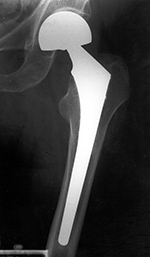

Total Hip Replacement

Total hip arthroplasty (THA) is the most common total hip replacement. It uses two components, a stemmed femoral component with a prosthetic femoral head and a prosthetic acetabular component (figure: modular total hip arthroplasty; figure: bilateral total hip arthroplasty). In 2011 there were 306,000 total hip replacements which is only second to 645,062 total knee replacements (AAOS). There were also estimated to be 105,509 partial hip replacements.

are modular. The acetabular shell, acetabular liner, femoral head, and femoral stem are separate pieces (figure: modular total hip arthroplasty). This allows the surgeon to customize each prosthesis for size and fit. Unfortunately, this can sometimes create problems at the interfaces between the modular components with disengagement and fretting. Classically, the articulating surface between the femoral head and the acetabular lining is metal (femoral head) against polyethylene (acetabular lining).

For patients younger than 65 with a normal life expectancy and adequate bone mass, cementless femoral stems are preferred (figure: bilateral total hip arthroplasty in 38 year-old man). It is possible that a femoral stem which has become well ingrown will not require revision, even if the acetabular component, and the articulating femoral head may need revision in the future. However, as in most cases with orthopedic surgery, the choice of components and the use of cemented or cementless femoral component depends on the surgeon's preference and experience. With any type of joint replacement, there is concern for its longevity and the need for ultimate revision or complete replacement. Revision surgery is usually not easy and may not have good results. Therefore, joint replacement is avoided as much as possible in younger patients and put off as long as is reasonable.

Regardless of the fixation used, the preferred

position of the femoral component is with the stem centered in the femoral

canal on the anteroposterior view. The center of

rotation of the prosthetic femoral head should be at the

level of the greater trochanter. The position of the

stem can vary somewhat depending on the patient’s preexisting

anatomy (Manaster, 1996). If the femoral stem tip is against the lateral femoral cortex, failure of the stem is more likely (Deshmukh, 2019). Surgeons performing hip arthroplasty have their own preferred methods for evaluating the arthroplasty results usually relying on standard radiography coupled with the individual patient's clinical presentation.

Total hip arthroplasty with porous coated stem |

67 year-old woman